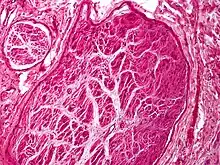

A traumatic neuroma is a type of neuroma which results from trauma to a nerve, usually during a surgical procedure. The most common oral locations are on the tongue and near the mental foramen of the mouth.[2] They are relatively rare on the head and neck.[3]

An essential step in the formation of a traumatic neuroma is injury to the perineurium. The perineum directs the growth of axons by acting as a surface that the axons cannot go through. If the perineurium is compromised, the axons may escape into the extraperineural space and arborize in an unregulated fashion.[4]